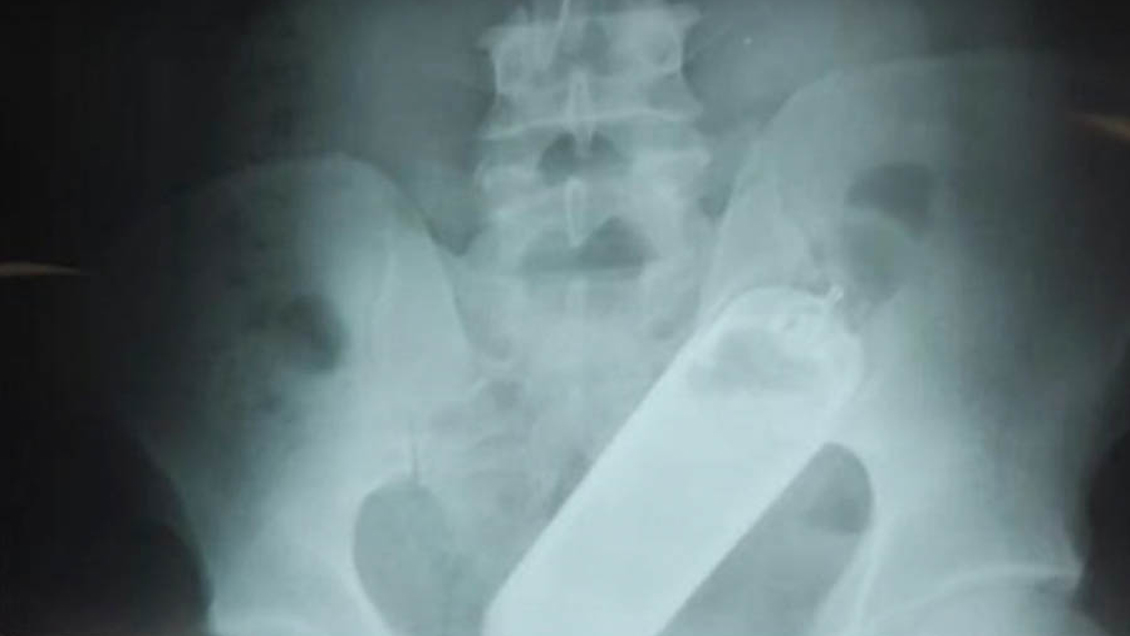

Los médicos interrogaron al paciente y luego le realizaron una radiografía que reveló que el hombre tenía un frasco en el recto, añadió.

Posteriormente, los médicos formaron un equipo de especialistas para extraerle en el quirófano el frasco que estaba dentro de un condón, precisó el portavoz del hospital.